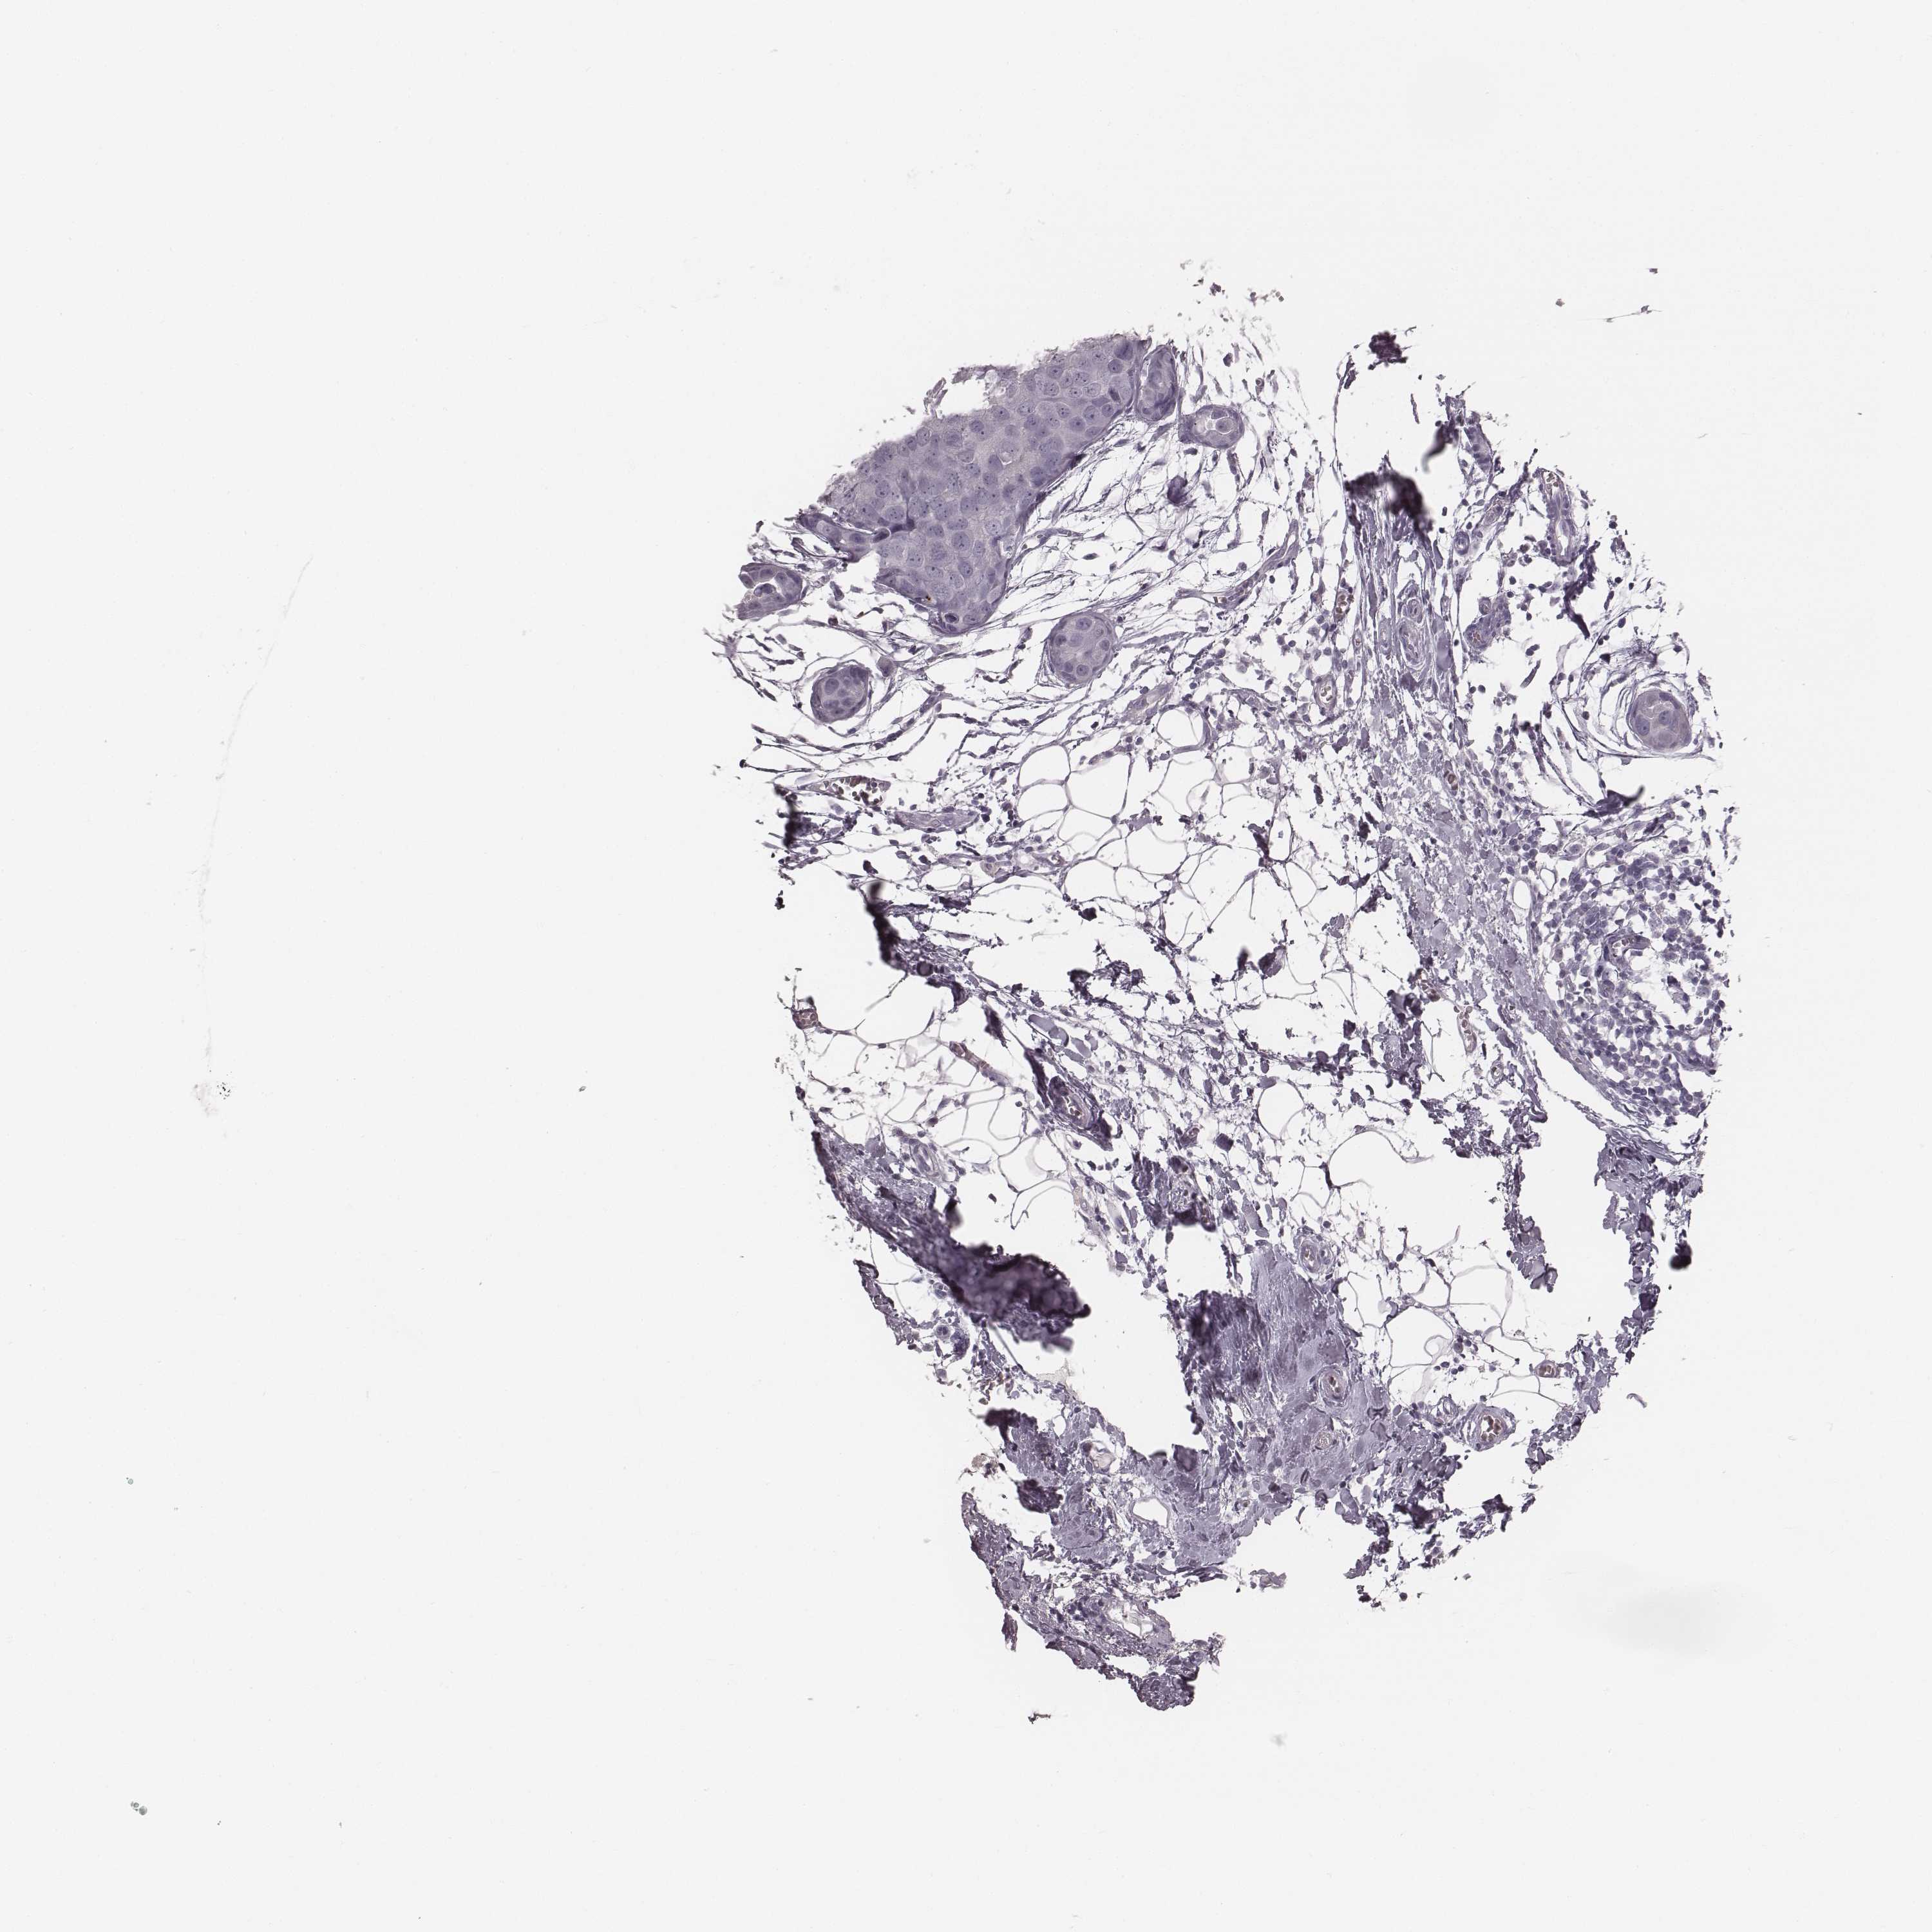

BRCA TCGA BRCA VALIDATION PROTEIN EXPRESSION

ANTIBODIES

AND

VALIDATION